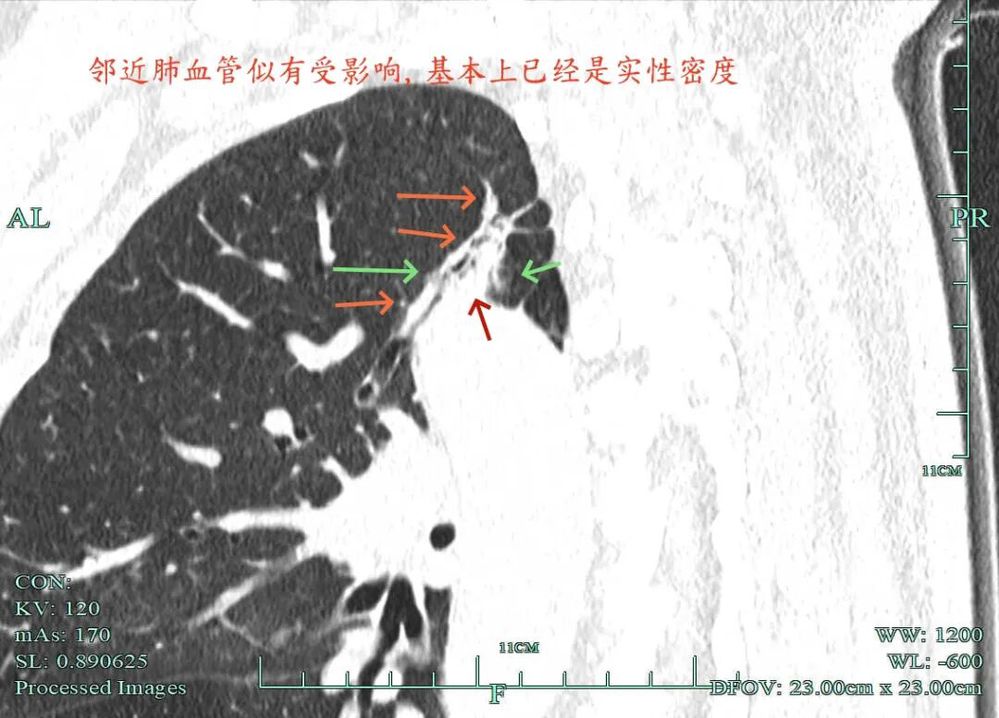

杭州市肿瘤医院影像展示与分析:

右上也有混合密度结节,实性部分缺乏膨胀性与收缩力,磨玻璃成分较淡,也偏糊,但持续存在仍得考虑肿瘤范畴可能性大。

此视角是混合密度,实性为主,贴胸膜近。